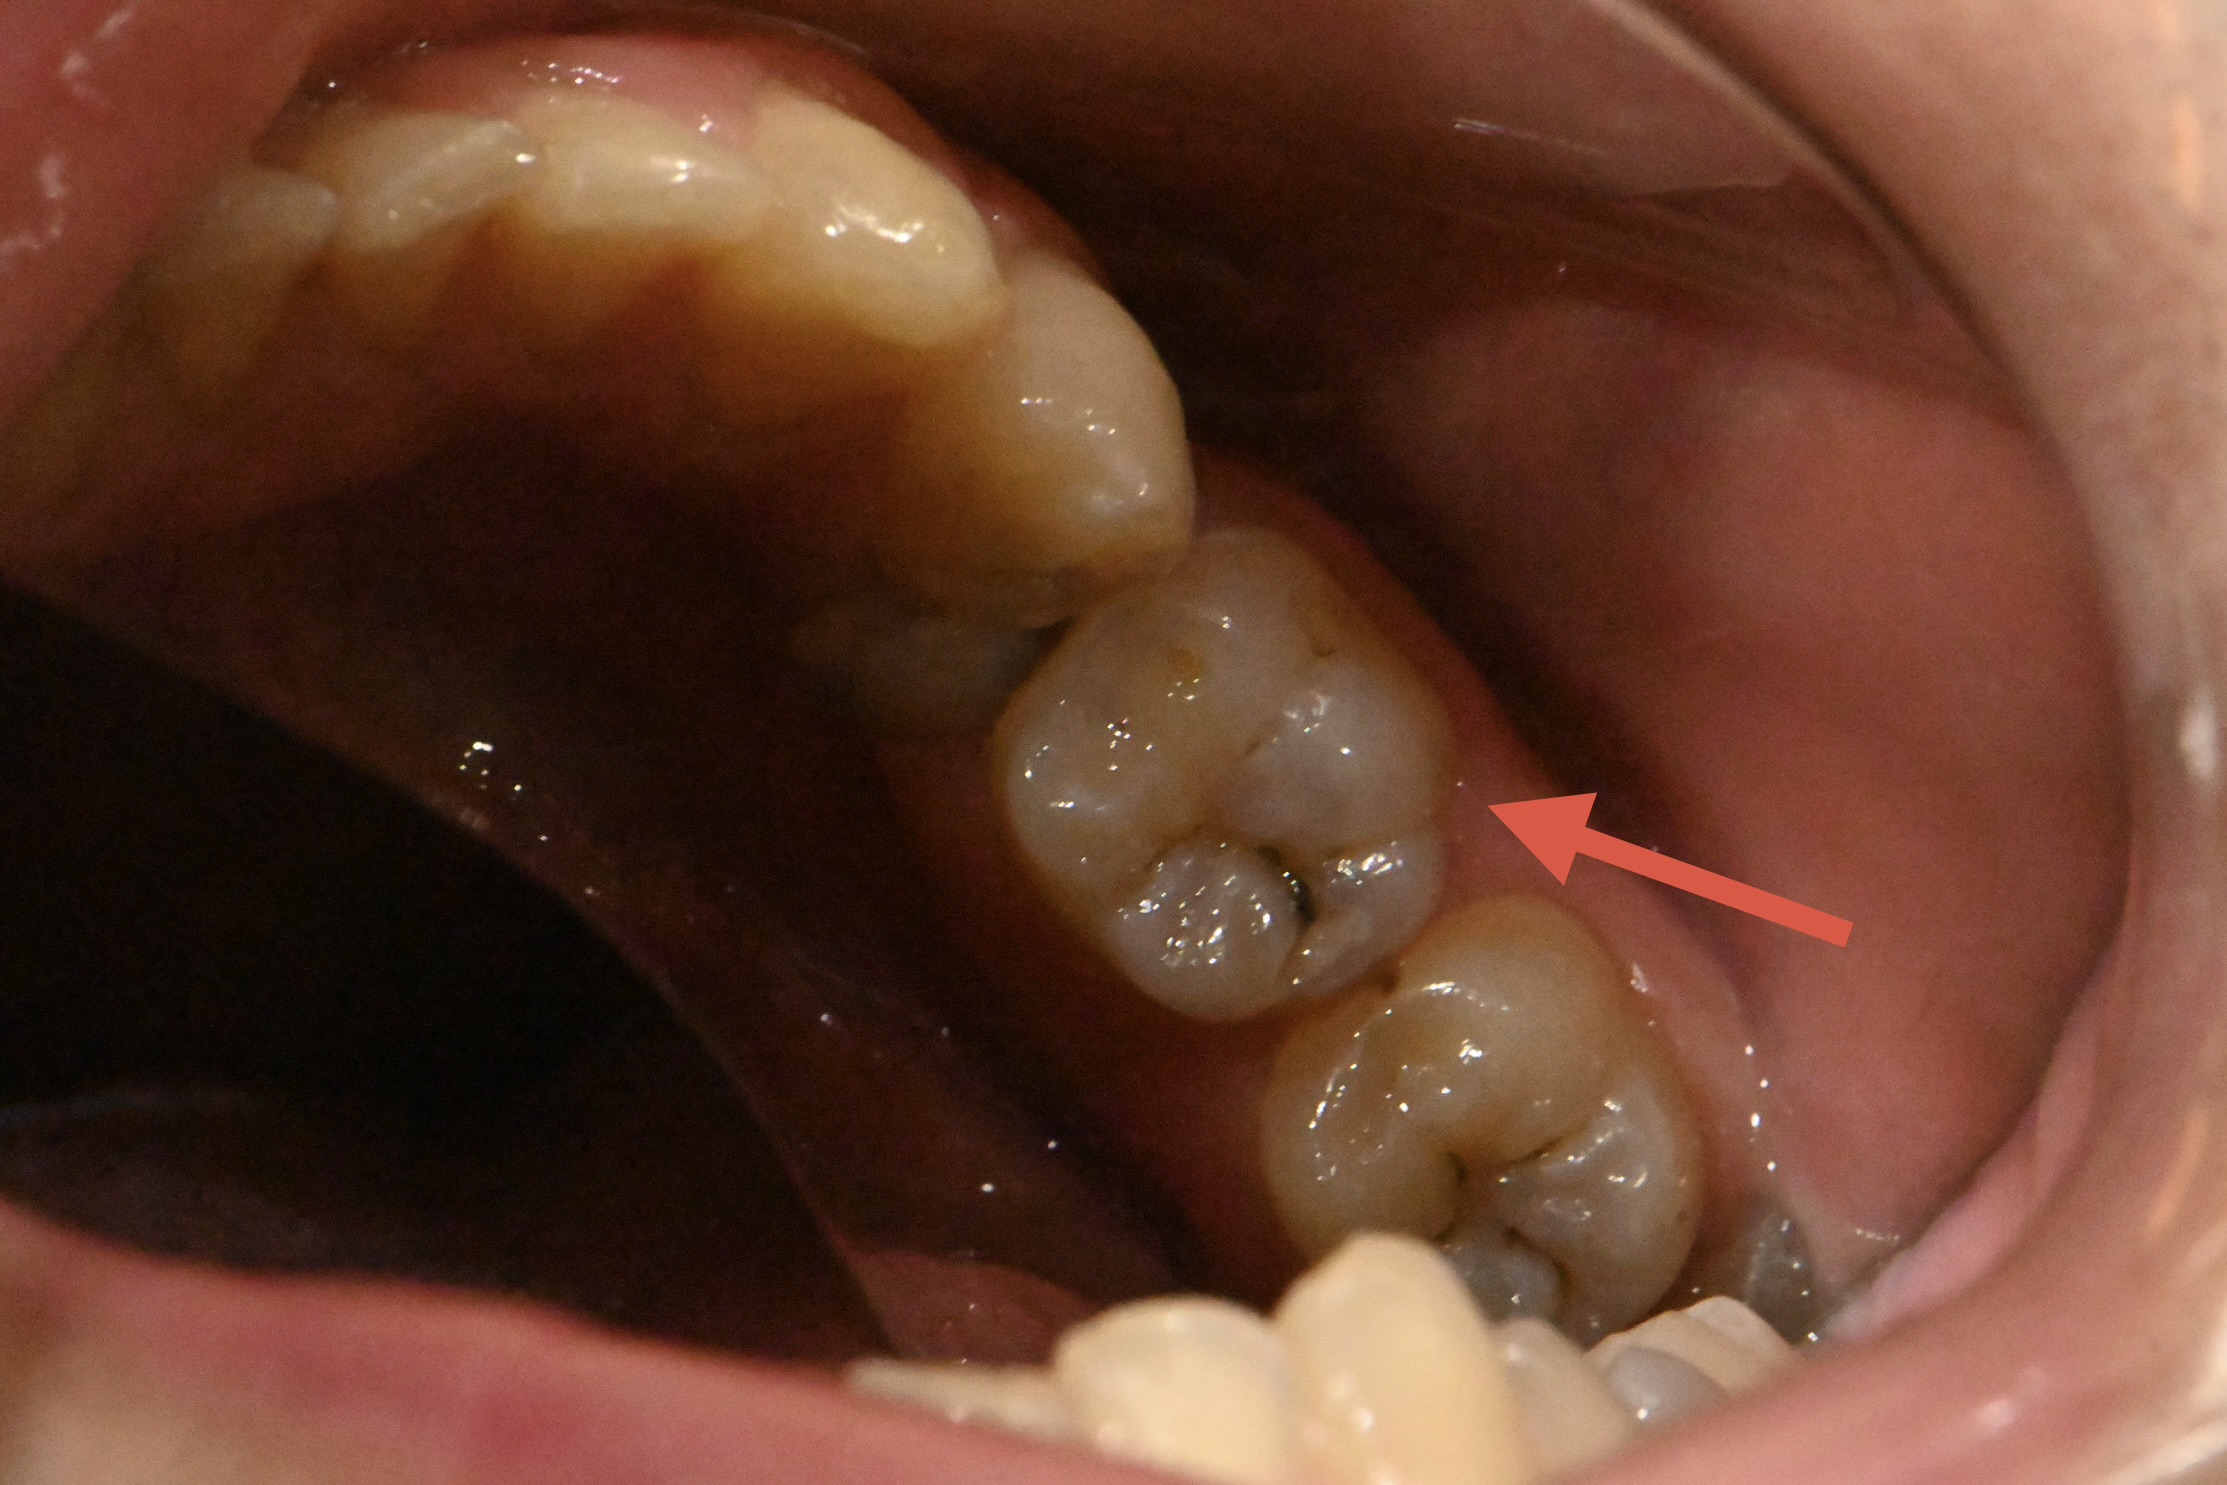

【治療前】左下第一大臼歯

MTA詰める前→詰めた後